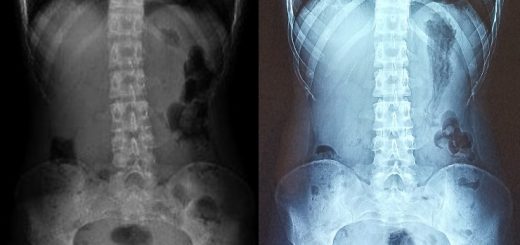

Prevention of Further Disc Degeneration and Preservation of Thoracic Kyphosis